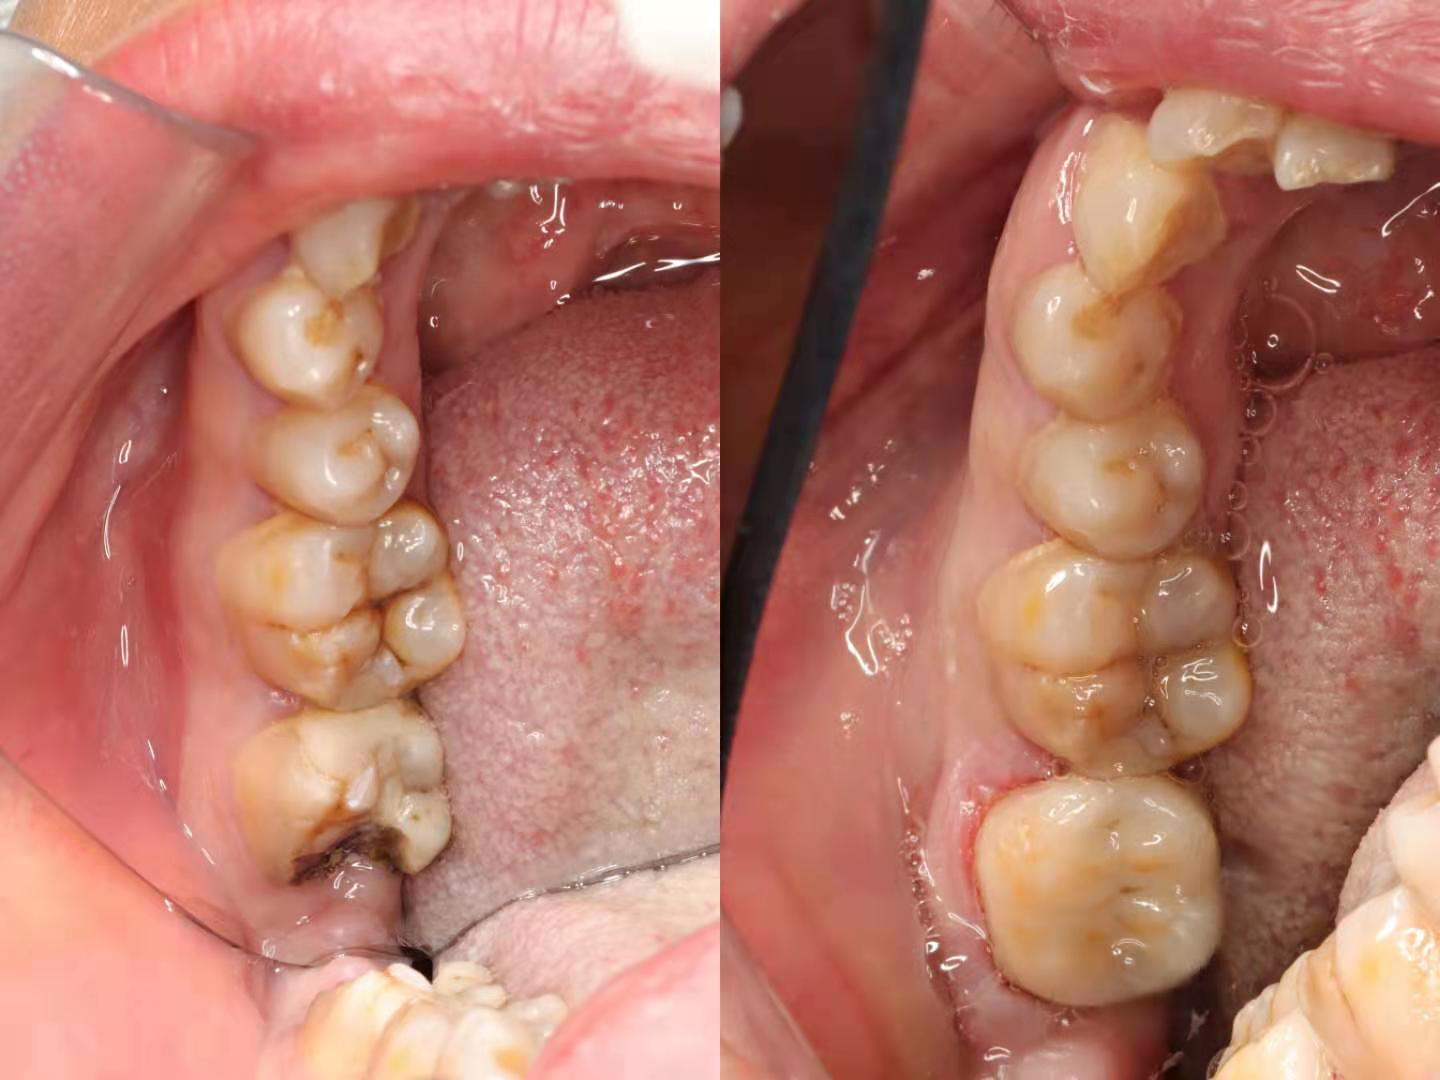

即刻粘接术后照

术前术后对比

针对相对大的牙体面积缺损、龋坏及多次充填治疗失败的患牙,利用数字化技术,CAD光学扫描得到精准数字模型,通过CAM技术打印出高精度修复体,利用橡皮章隔离技术确保了高强度的粘接,瓷嵌体修复远期治疗效果得到了保障。